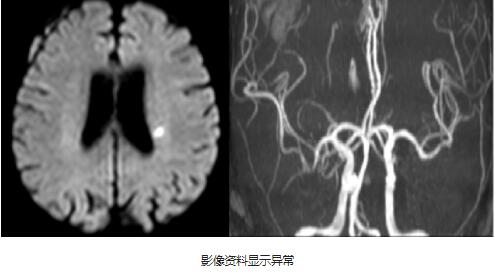

我院副院长、神经内科专家王展航接诊了患者,听了家属的描述后,立即为患者安排了影像检查。急诊DWI显示左侧放射冠偏急性梗死灶。根据家属的描述,患者从发病到就医已12小时,超过静脉溶栓时间窗(4.5小时之内)。王展航根据患者的情况,给予了药物治疗,并制定了一系列的康复计划。